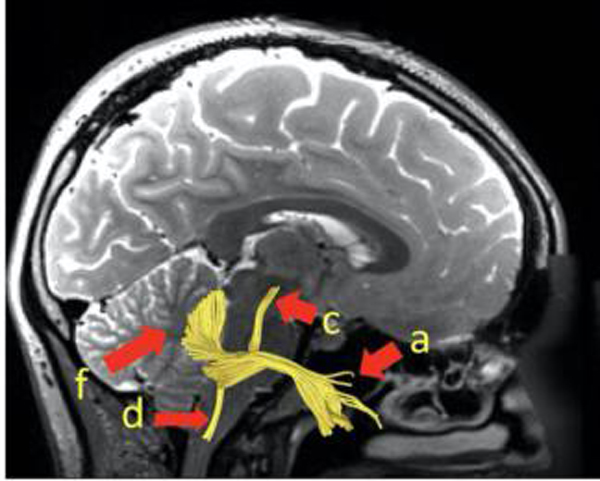

在历经医学影像数据前期处理、纤维束示踪术方法对比、应用参数逐个调试及不同示踪结果对比分析等诸多重复杂环节步骤,并经过反复多次的运行测试,谢国强医生科研团队最终成功追踪出三叉神经纤维束自脑干内段至分支段形态,系在专业领域内较早通过纤维示踪技术追踪三叉神经形态的文献报道。日前,该项研究成果以陕西省核工业二一五医院为第一单位正式发表于《NeuroImage:Clinical》(影响因子4.350)杂志,不仅显示二一五医院在医学影像数据处理方面的一大进步,同时也彰显了科研水平的持续提升。